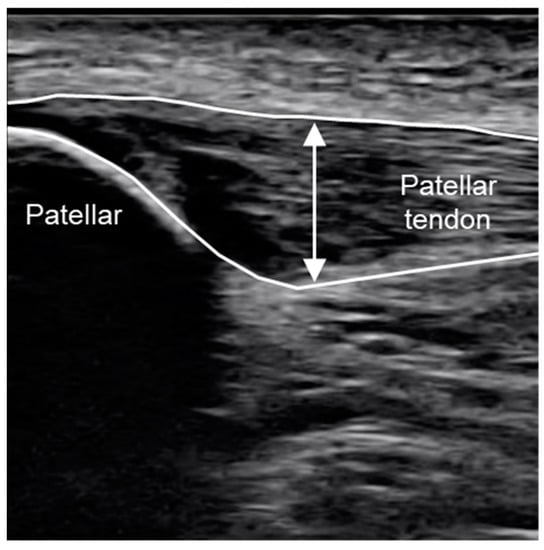

| Patella Tendon Thickness (mm) | 0.93 | ± | 0.26 | 0.93 | ± | 0.26 | 0.93 | ± | 0.26 | 0.92 | ± | 0.26 |